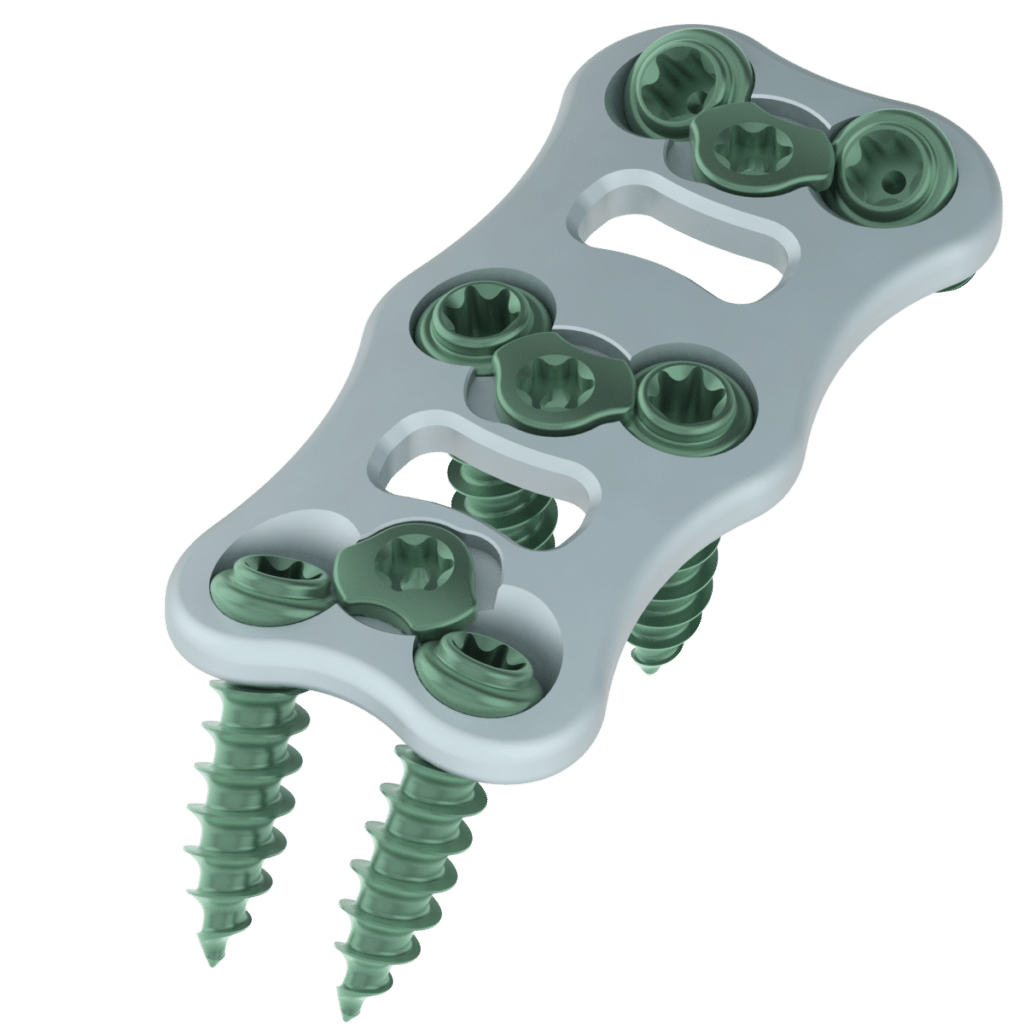

HCM Orthocare is a trusted and reliable manufacturer, supplier and exporter of cervical spine plates used in spinal surgery. The cervical spine plate is a medical device used to support and stabilize the cervical spine after a spinal injury, fracture, or fusion surgery. It is designed to provide stability to the spine and promote proper healing. HCM Orthocare produces high-quality cervical spine plates that are made from premium quality materials, such as titanium and stainless steel, which have been tested and approved for their strength, durability, and biocompatibility.

As a leading manufacturer of cervical screws, HCM Orthocare is committed to providing high-quality products that are designed to promote successful surgical outcomes. Our team of experts utilizes advanced technologies and processes to ensure precision and accuracy in the manufacturing process, and we work closely with medical professionals to develop innovative products that meet the specific needs of each patient. Contact us today to learn more about our cervical screw products and how we can assist you in achieving successful surgical results.

Specification:

- Available in Length : 21 mm to 70 mm (2-2 Difference)

- Available in Titanium

Specification:-

Size: Available in different sizes

Plate Material: Titanium

Screw Material: Titanium

Number of Holes on Plate: 4 or 6 or 8 holes